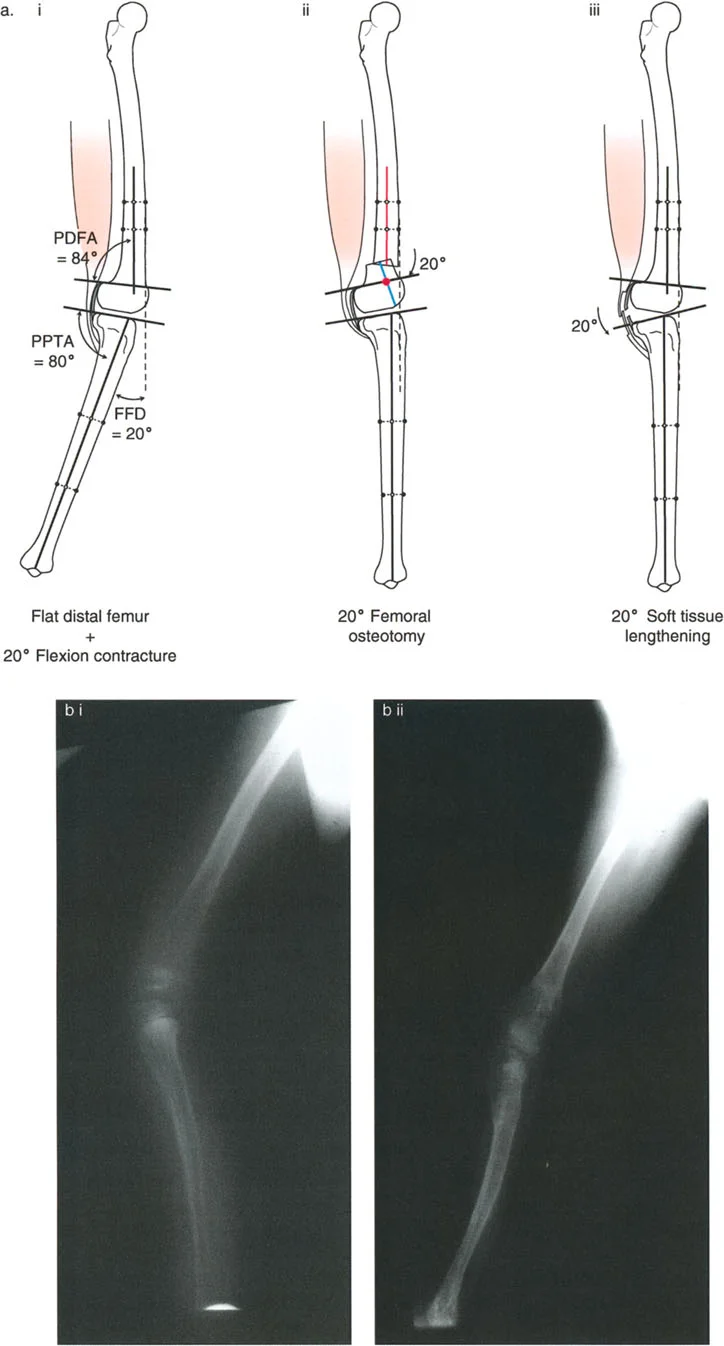

تصحيح تحدد حركة الركبة (Flexion Deformity - FFD)

تحدُّد حركة الركبة هو عدم القدرة على مد الركبة بالكامل. يمكن أن يكون سببه عظميًا أو ناتجًا عن تقلص في الأنسجة الرخوة.

- التشخيص الدقيق: يجب تحديد ما إذا كان تحدد الحركة ناتجًا عن تشوه عظمي (تقوس أمامي في الفخذ أو الساق) أو تقلص في الأنسجة الرخوة (الأوتار الخلفية، محفظة المفصل).

- قطع العظم التمديدي (Extension Osteotomy):

- إذا كان التشوه عظميًا، يتم إجراء قطع عظم تمديدي في عظم الفخذ أو الساق لتصحيح التقوس.

- الأستاذ الدكتور محمد هطيف يؤكد على أهمية عدم تصحيح الساق بأكثر من 90 درجة PPTA لتجنب فقدان الميل الخلفي الطبيعي للساق.

- تحرير الأنسجة الرخوة (Soft Tissue Release):

- إذا كان السبب هو تقلص الأنسجة الرخوة، فقد يتم إجراء إطالة للأوتار أو تحرير لمحفظة المفصل.

تصحيح الركبة الارتدادية (Recurvatum Deformity - Hyperextension)

الركبة الارتدادية هي فرط البسط في الركبة. غالبًا ما تكون غير مصحوبة بأعراض في الأشخاص ذوي العضلات السليمة، ولكنها قد تسبب مشاكل في حالات ضعف العضلات أو التشوهات العظمية.

- التشخيص: يجب تحديد ما إذا كانت الارتدادية عظمية (تقوس خلفي في الفخذ أو الساق) أو ناتجة عن رخاوة في الأنسجة الرخوة أو ضعف عضلي.

- قطع العظم الانثنائي (Flexion Osteotomy):

- إذا كان التشوه عظميًا (تقوس خلفي)، يتم إجراء قطع عظم انثنائي في عظم الفخذ أو الساق لتصحيح الارتدادية.

- الأستاذ الدكتور محمد هطيف يشدد على أهمية عدم استخدام قطع عظم الفخذ الانثنائي لتصحيح ارتدادية الساق، والعكس صحيح، لتجنب الانزلاق الخلفي أو الأمامي للركبة.

- اعتبارات خاصة: في المرضى الذين يعانون من ضعف عضلي (مثل شلل الأطفال)، قد يحتاج التصحيح إلى فرط تصحيح بسيط (overcorrection) إلى وضعية انثناء لضمان ثبات الركبة ومنع فرط البسط غير المتحكم فيه.